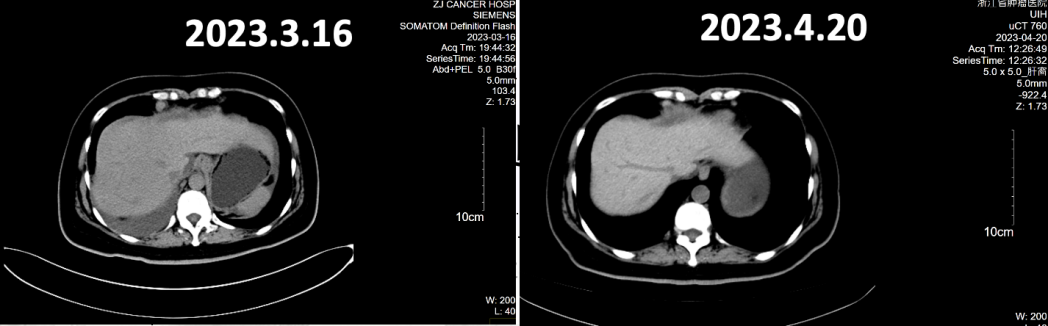

全腹CT(2023年3月16日):盆腔见囊实性灶,肝表面、大网膜及盆底腹膜多发结节灶,考虑转移,较前似饱满。腹盆腔积液,较前增多。右侧斜裂胸膜不均匀增厚,较前明显,转移考虑。右侧胸腔积液,较前增多。右侧心膈角增大淋巴结,较前缩小,考虑转移。疗效评价为疾病进展(PD)。

全腹CT:肝表面、腹膜、肠表面及盆腔系膜多发结节灶及增厚,考虑转移,部分较前稍缩小;腹盆腔积液,较前稍吸收。右侧斜裂胸膜不均匀增厚,较前缩小,转移考虑。右侧胸腔少量积液,较前明显吸收。双侧心膈角增大淋巴结,较前缩小,考虑转移。疗效评价为部分缓解(PR)。